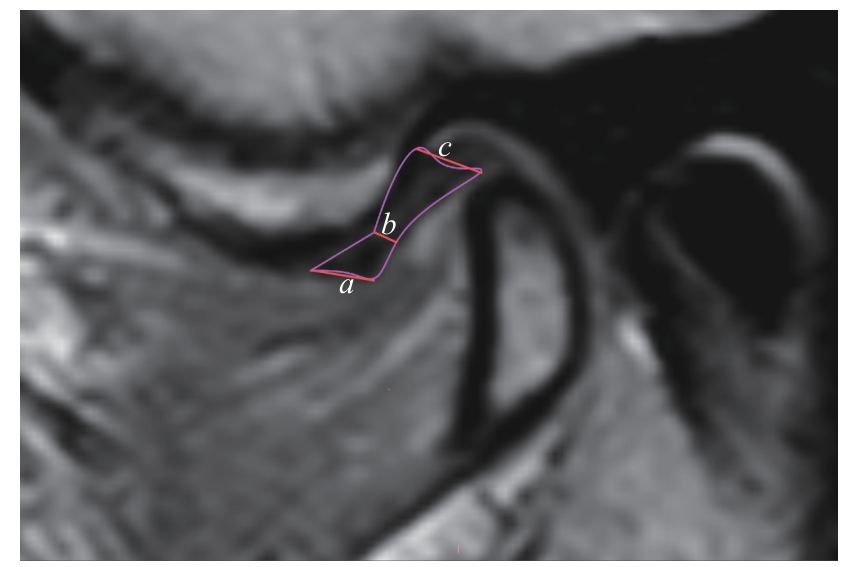

| 图5 颞下颌关节盘厚度测量 Note: An oblique sagittal PDWI image. a—anterior band thickness; b—intermediate zone thickness; c—posterior band thickness. |

| Fig 5 Measurement of articular disc thickness |